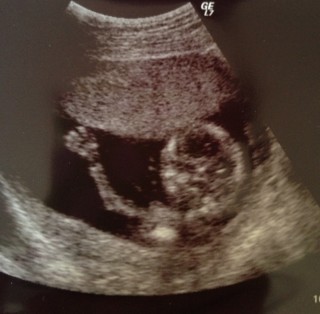

初めての経腹プロープ。 蹴ったり、しゃっくりしたり、回ったり、胎盤にパンチしたりすごい勢いで動いていたので、いろんなポーズが撮れて、超音波写真がすごい枚数に…笑

看護師さんが「指の骨、見えるかなぁ~?」と言ったら、パーで手を振ってくれました!! 一緒に見ていた義母と大爆笑でした。面白い子が産まれそう!

そろそろ性別が分かり出す頃だと看護師さんに聞いたので先生に聞いてみたら、男の子だと判明!3人目で初の男の子だったので家族で大喜びしました。

CRL 76.5 体重50g とのこと。

体重もわかるんですね。